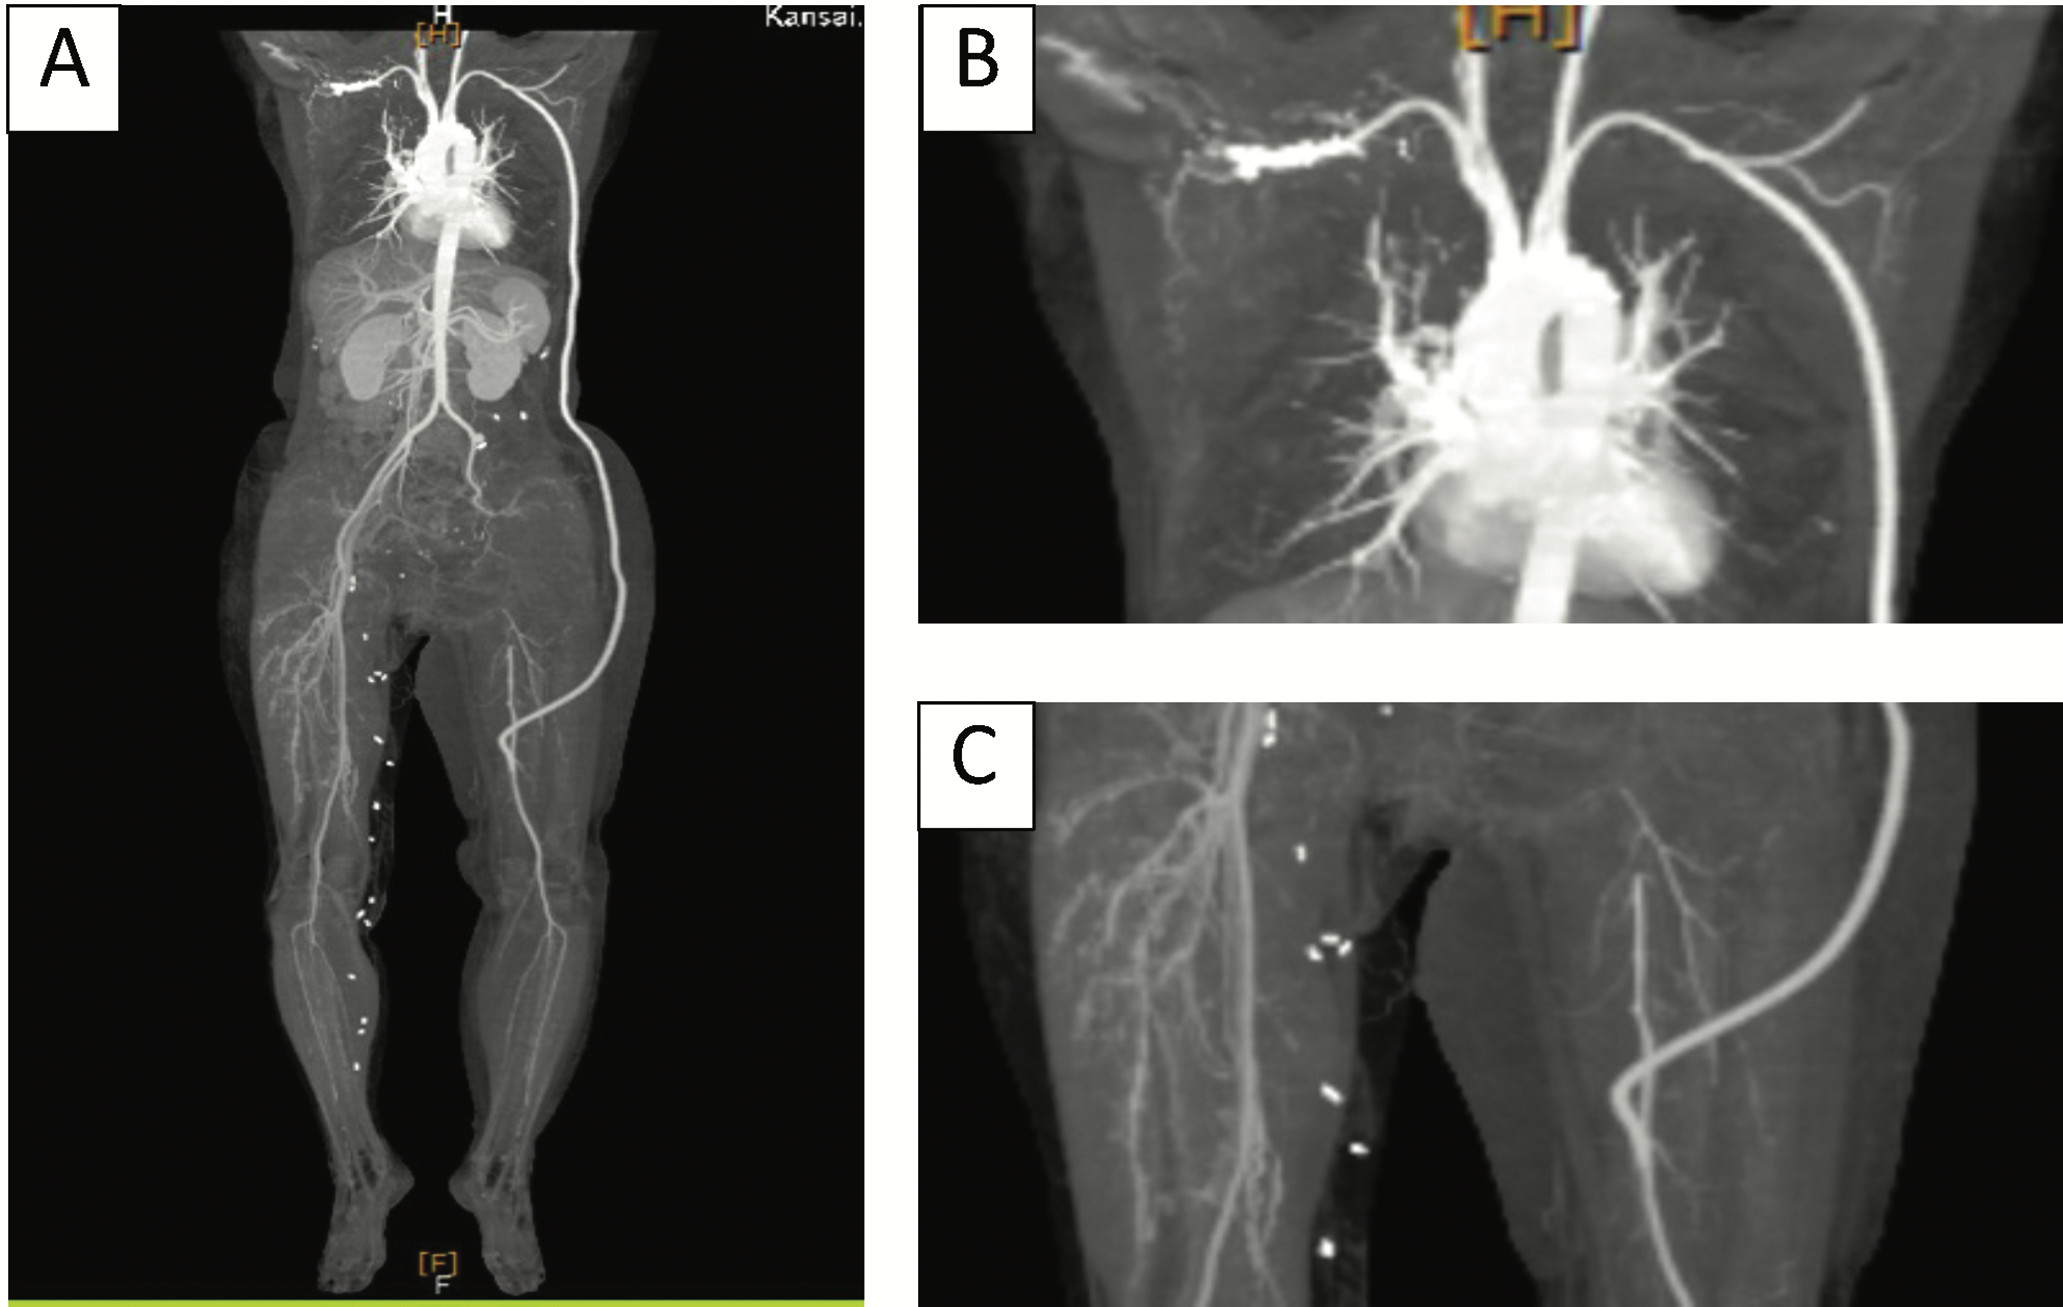

The patient underwent left subclavian artery–to–superficial femoral artery bypass surgery (using 6-mm heparin-bonded ePTFE graft: PROPATEN, W.L. Gore, USA) 3 weeks prior to tumor resection. Postoperative computed tomography (CT) revealed patent bypass graft (Figure 3).